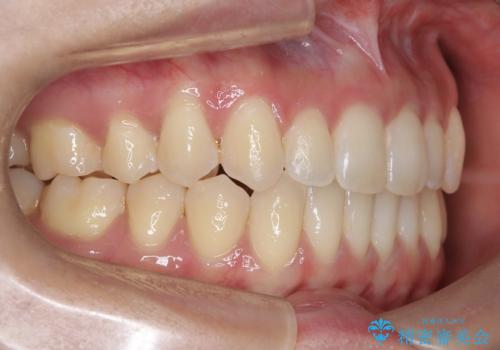

再矯正 前歯のガタツキをマウスピース矯正で治療したい

- 前に矯正治療をしたが、後戻りしてガタツキが出てきたので、治したいとのことで来院されました。

ワイヤー治療とマウスピース矯正、2通りの治療を提案させていただき、マウスピース矯正治療を希望されましたので、インビザラインによる治療を開始しました。

前歯のガタツキを改善する治療法として、マウスピース矯正が適していることが多いです。

マウスピース矯正は、金属製のブラケットやワイヤーを使用せずに、透明なマウスピースを装着して歯を移動させる方法です。そのため、目立たず、痛みも少ないです。